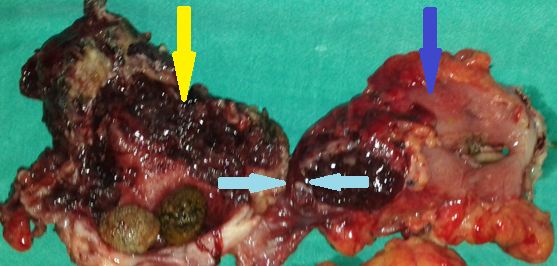

Yellow arrow — Thick-walled gallbladder with gallstones. Blue arrow — Stomach segment. Light blue arrows — Cholecystogastric fistula (Courtesy Dr. V. Penopoulos)